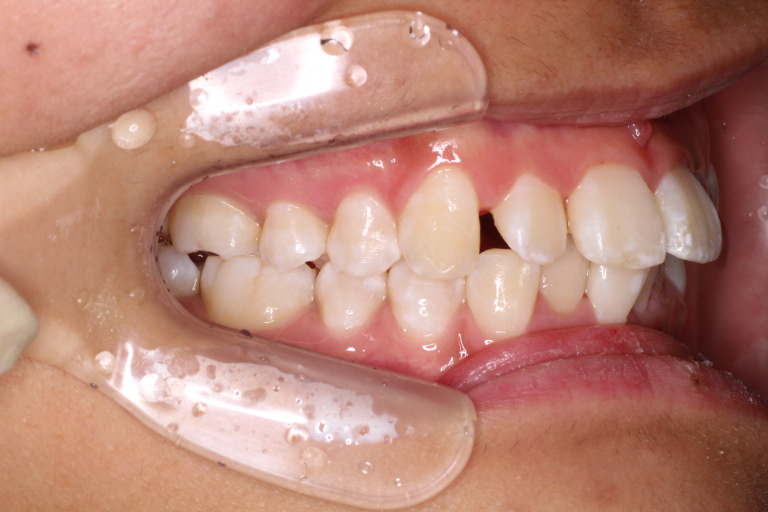

カリエールモーションが終わった時の口腔内写真です。

上の奥歯が後ろに下がったおかげで前歯には隙間ができています。

左の噛み合わせを見ると下の歯と歯の間に上の歯が入り込んでいることがわかります。

1歯対2歯の関係です。

右の噛み合わせを見ると左の噛み合わせより少し多めに奥歯を後ろに下げていることがわかります。

オーバーコレクションといって少し戻ることを想定して多めに動かしておくことを言います。